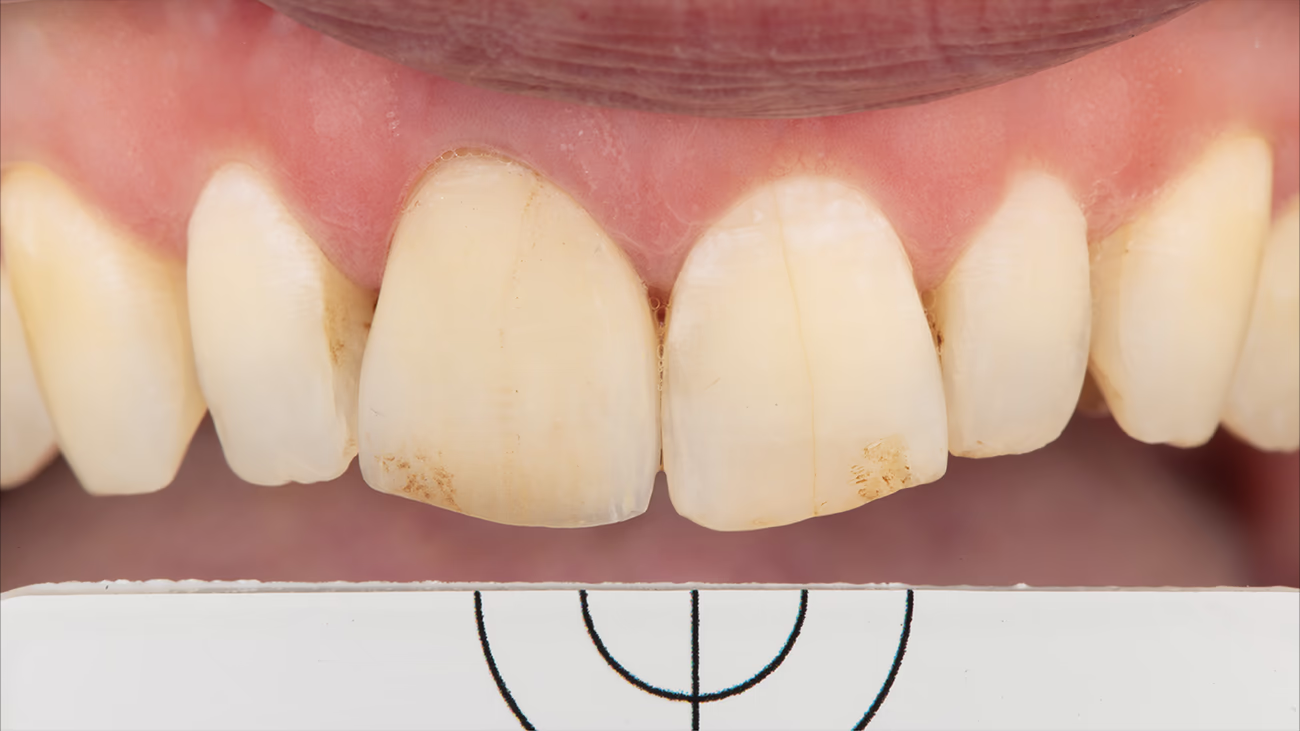

На першому етапі лікування було зроблено внутрішньоротове фото зубів з поляризаційним фільтром та сірою картою як початкове значення клінічної ситуації.

Перед фіксацією тимчасової реставрації на зуб 11 зробили фото обробленої кукси зуба з поляризаційним фільтром і сірою картою. Це додаткова інформація для зубного техніка про стан та колір кукси зуба.

Під час наступного візиту пацієнта в клініку робимо примірку та фіксацію керамічної рестарації зуба 11.

Першим кроком було зняття тимчасової реставрації зуба 11 і полірування кукси від залишків адгезиву.

Примірка постійної реставрації на суху по верхню (Dry Fit) дає змогу контролювати точність прилягання конструкції.